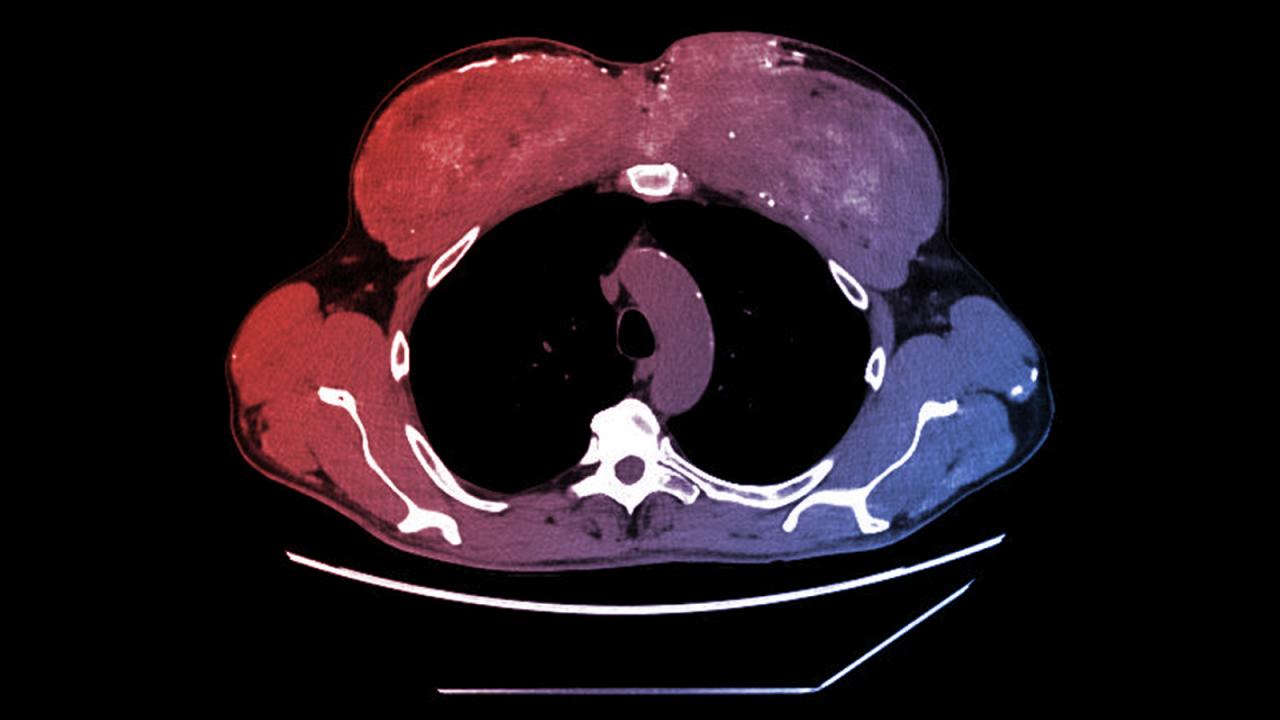

A CT-vizsgálat feltárta, hogy a férfi mellizmában sűrű, elmeszesedett területek jelentek meg, épp ott, ahová évekkel korábban izomnövelő olajat fecskendezett. Hasonló kalciumlerakódásokat találtak a vesében, hasnyálmirigyben, gyomorban, sőt, a tüdőben is heges, szokatlan elváltozásokat észleltek. A férfit intenzíven kezelték vizelethajtóval, intravénás folyadékkal, szteroiddal és kalciumcsökkentő gyógyszerrel; átmenetileg javult, de három héttel később újra veszélyesen megemelkedett a vérkalciumszintje, ezért visszakerült a nefrológiára.

A férfi fizikális vizsgálata feltűnő izomdeformitást mutatott a felkarján és mellkasán. Ekkor vallotta be, hogy harminc éve rendszeresen kapott – valószínűleg tesztoszteront és olajat tartalmazó – izomnövelő injekciókat. Az utolsó adagot két évvel a tünetek előtt kapta. A vérvizsgálat kizárta a hormonális és daganatos okokat, ezért izombiopsziára került sor, amely igazolta, hogy az izomban szilikonszerű, olajalapú anyag és jelentős mennyiségű kalcium található. A szintolként ismert szer olajat tartalmaz, amelyet az izomba fecskendeznek pusztán látványos „felfújás” céljából.